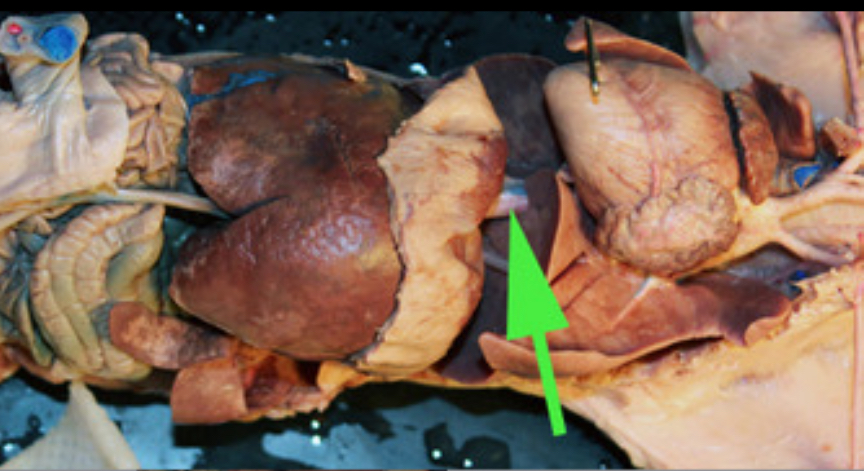

The organ marked by the green arrow arrow is the Spleen

The organ indicated by the green arrow is the SPLEEN